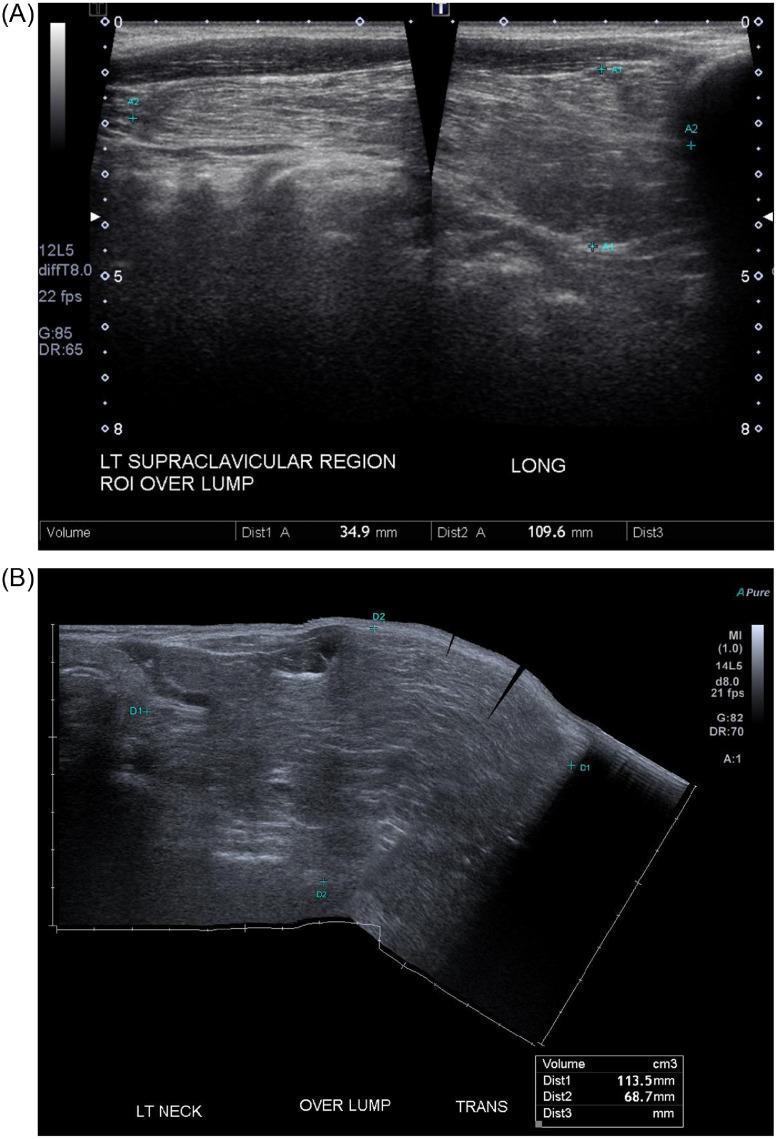

Lipomas are benign and very common subcutaneous tumors of adipose tissue, which may occur anywhere in the body. Lipomas in head and neck regions are extremely rare. A giant neck lipoma is classified as a lesion greater than 10 cm in one dimension or weighing more than 1000 g. In this case report and review of the literature, a 66-year-old male with likely diagnosis of neck lipoma was under 5-year surveillance prior to development of giant neck lipoma. Computed tomography provided critical insight in the extent of neck mass in relation to surrounding structures in assessing possibility of malignancy and in guiding appropriate management.

脂肪瘤是一种常见的良性皮下脂肪组织肿瘤,可发生于身体的任何部位。头颈部脂肪瘤极为罕见。巨大颈部脂肪瘤是指在某一维度上大于10厘米或重量超过1000克的病变。在本病例报告及文献回顾中,一名66岁男性在诊断为颈部脂肪瘤后,在发生巨大颈部脂肪瘤之前接受了5年的监测。计算机断层扫描对于评估颈部肿块相对于周围结构的范围、判断恶性可能性以及指导适当的治疗提供了关键的见解。